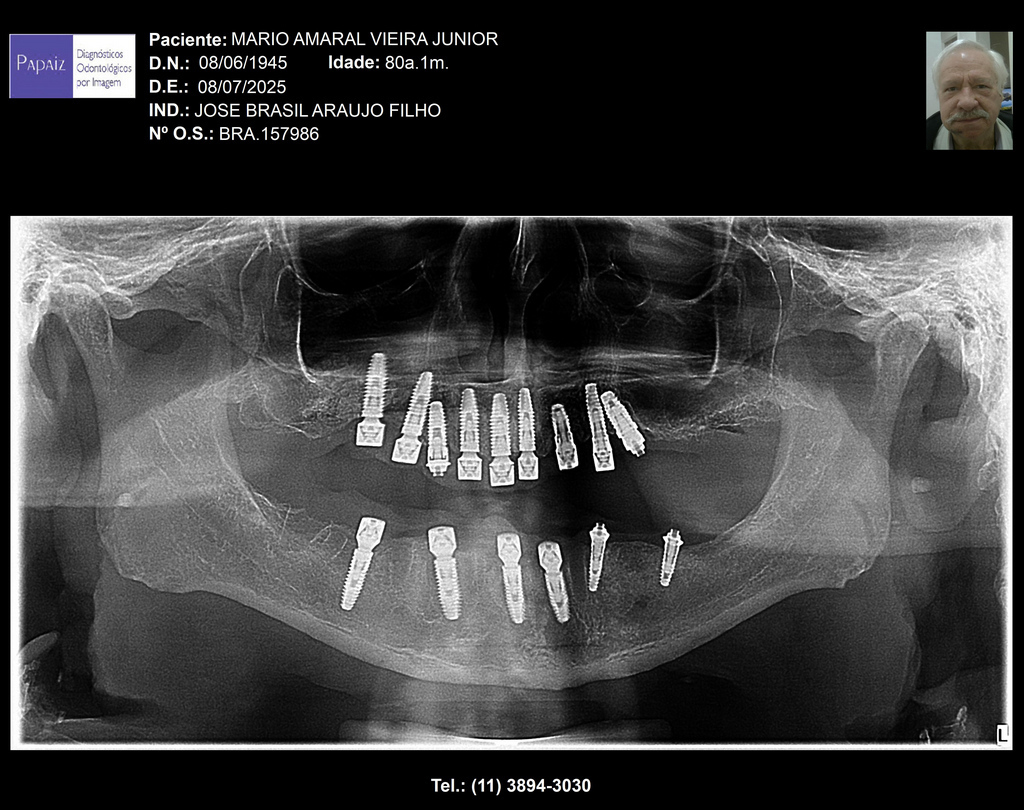

PRÓTESE TOTAL FIXA EM IMPLANTES

M.A.V.J.